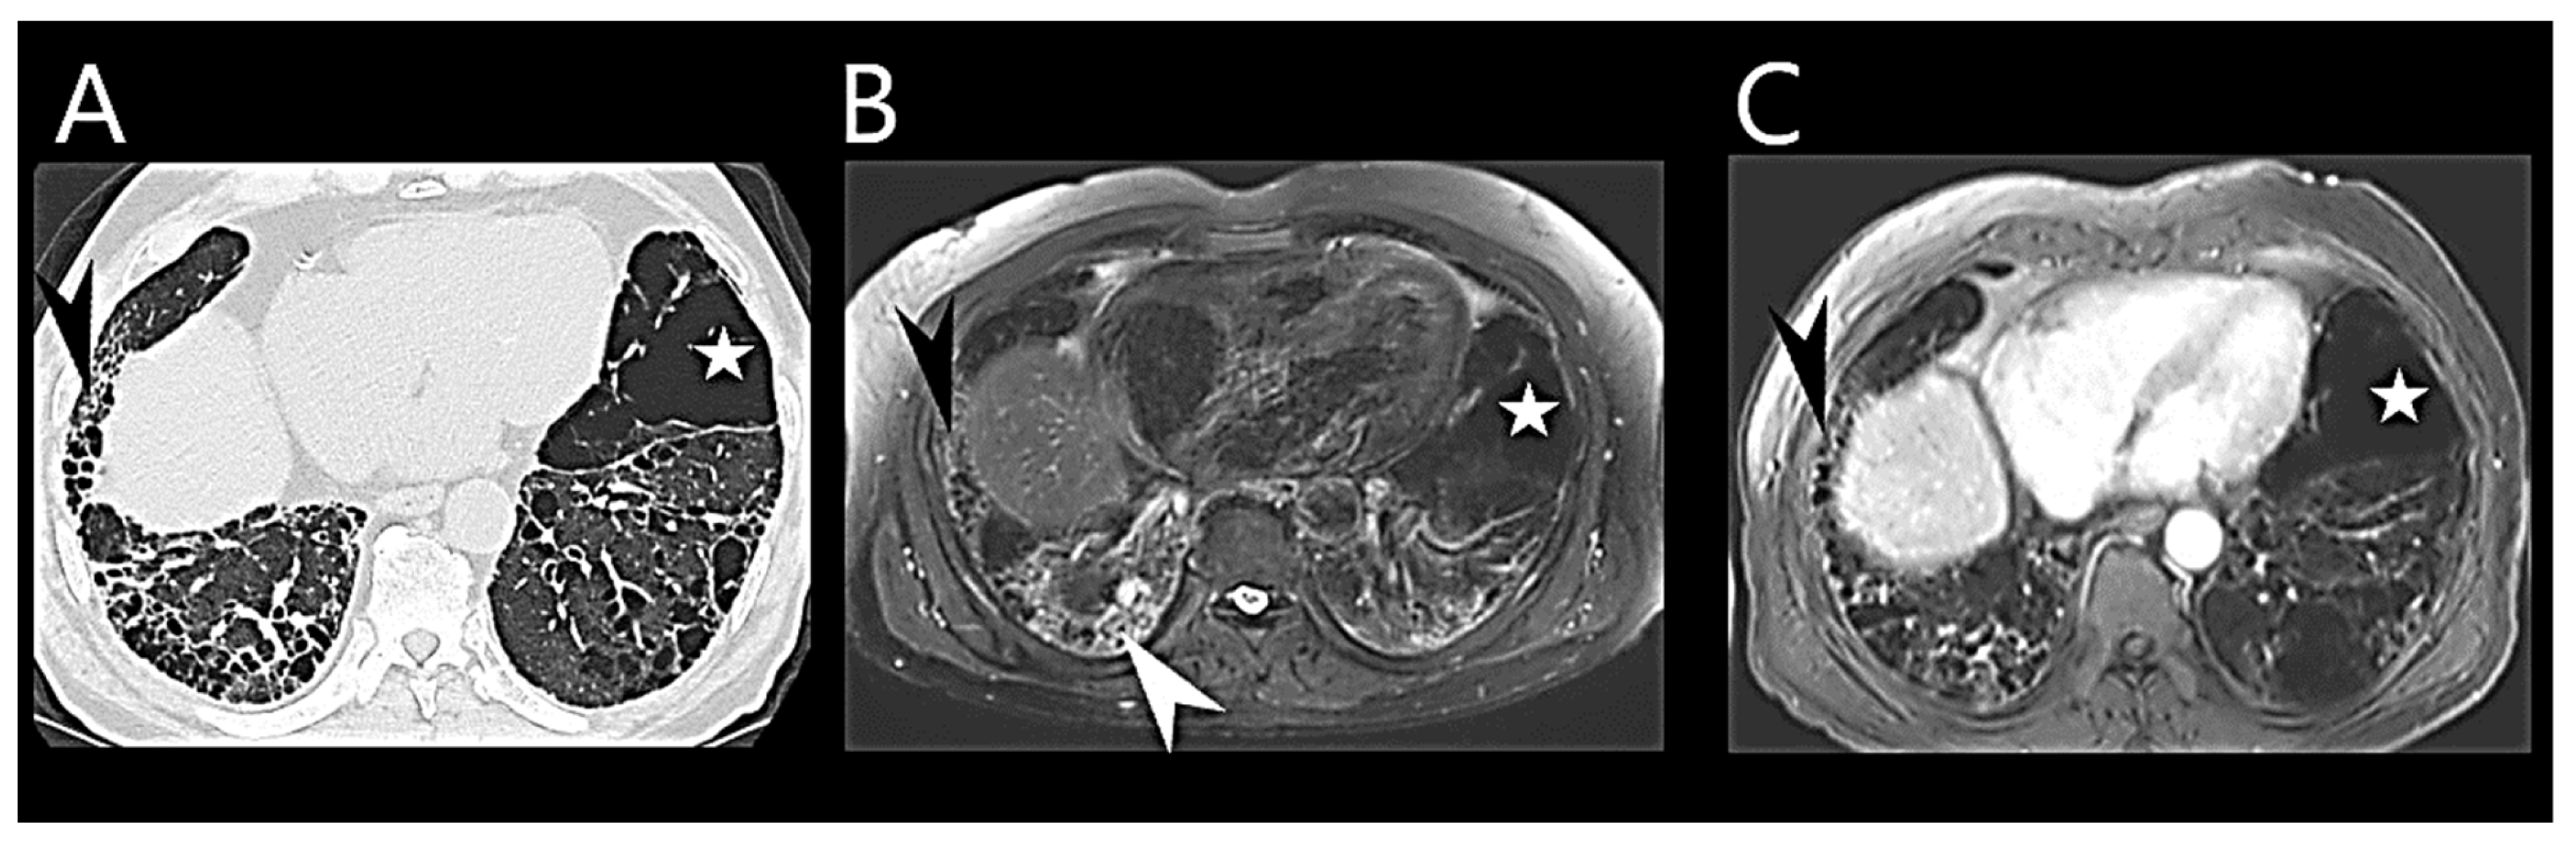

6.4. Chest Computed Tomography

6.6. Cardiac Magnetic Resonance Imaging